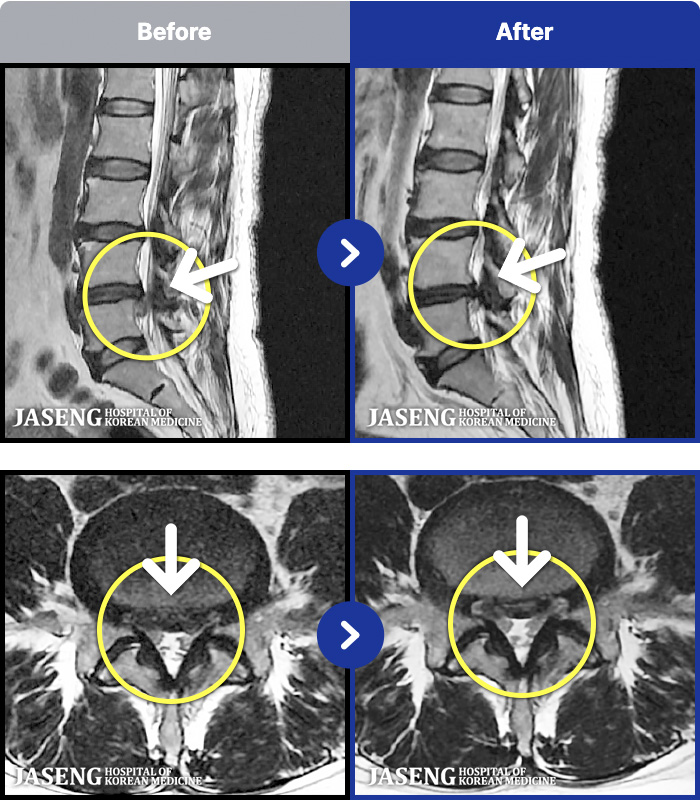

[뱸] 19.11.28~25.05.06